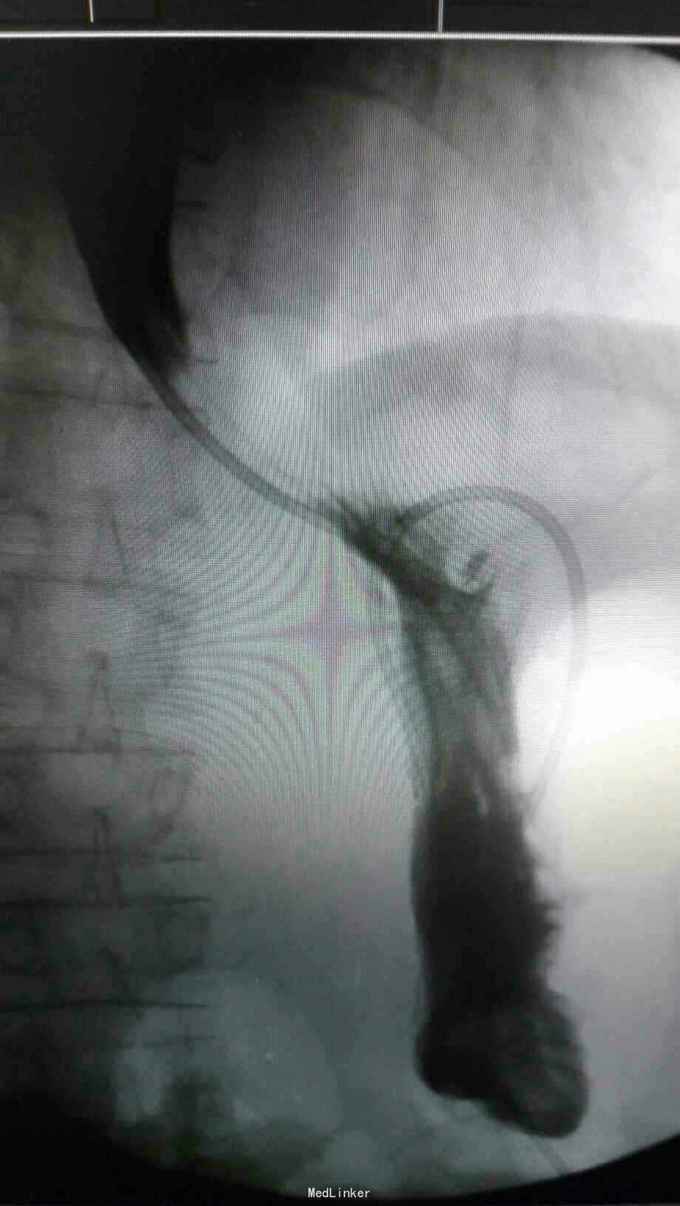

查体:入院后查体腹部平软,未见胃肠型,上腹部正中部可见20cm陈旧性瘢痕,腹部无压痛及跳痛,无肌卫;叩诊鼓音,肝脏及脾脏肋下未及;肝肾区无叩击痛,移动性浊音阴性,肠鸣音弱,1-2次/分。 检查:本次入院后查:WBC:9.2*10^9/L,Na:132mmol/L,余指标基本正常。电子胃镜:胃大部切除术后改变(毕II)吻合口粘膜充血水肿明显,直径约1.2cm,分别尝试进入输入袢及输出袢,见肠腔无明显狭;上腹部增强CT:1胰十二指肠切除术后;2肝脏多发小囊肿;3腹腔内未见明显感染及肿瘤转移征象。上消化道造影:残胃形态、扩张可,未见明显潴留液,蠕动较弱,中远部充盈不佳,胃小肠吻合口宽约1.2cm,未见狭窄及碘水渗漏。胃排空较慢。